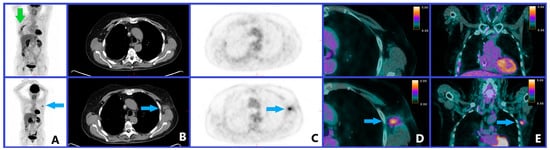

4. Medical Imaging: Baseline Examination

5.5. Abscopal Effect